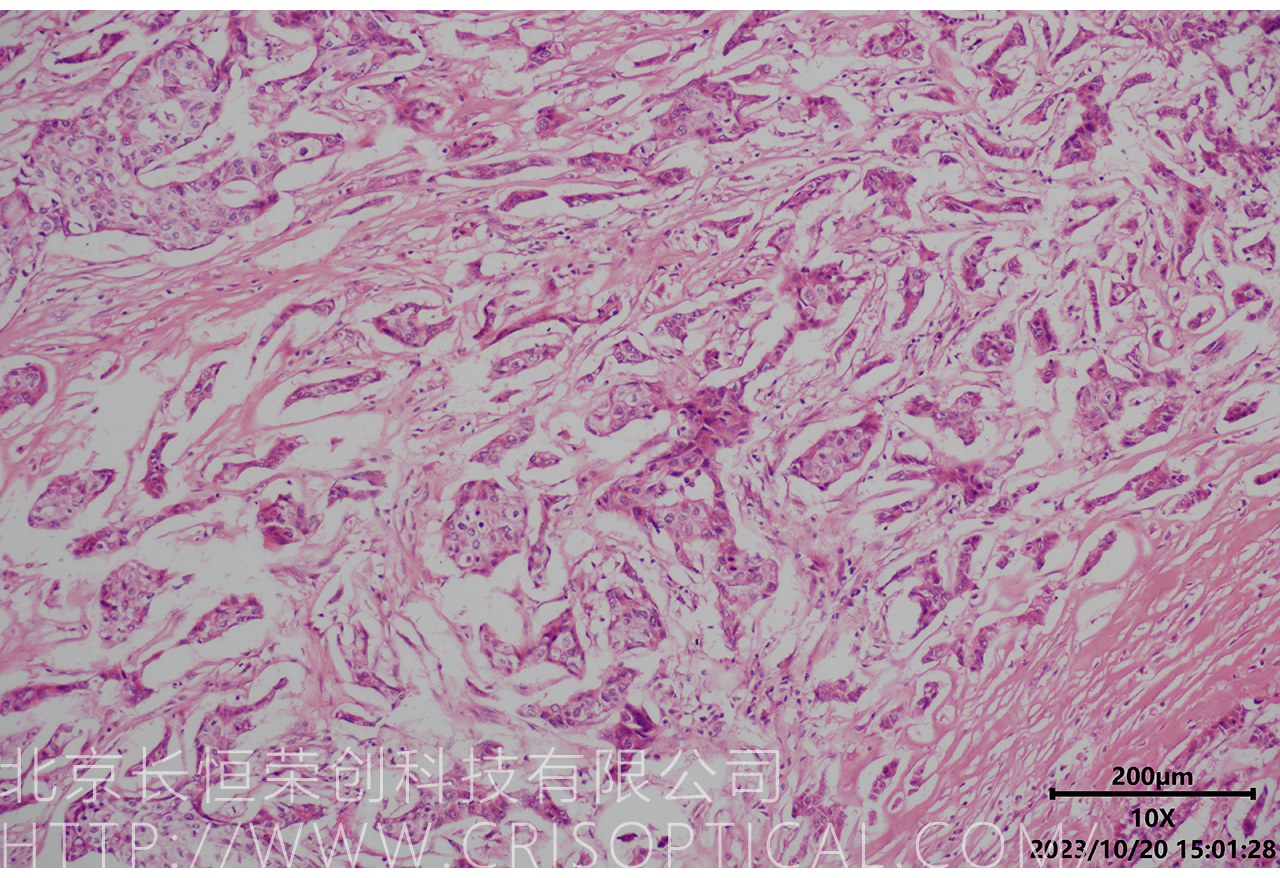

病理切片觀察是一種重要的醫(yī)學(xué)實(shí)踐,通過對(duì)組織和細(xì)胞切片的

顯微鏡觀察,幫助醫(yī)生診斷疾病、評(píng)估病情和制定治療方案。病理切片觀察在

臨床醫(yī)學(xué)、癌癥診斷、外科手術(shù)和疾病研究中發(fā)揮著關(guān)鍵作用。

腫瘤診斷:對(duì)癌癥和其他腫瘤的病理切片觀察是確定腫瘤類型、分級(jí)和分期的關(guān)鍵步驟。醫(yī)生通過觀察組織樣本中的細(xì)胞形態(tài)、核形狀、分裂活性和其他特征,可以識(shí)別腫瘤的類型,幫助決定治療方法。